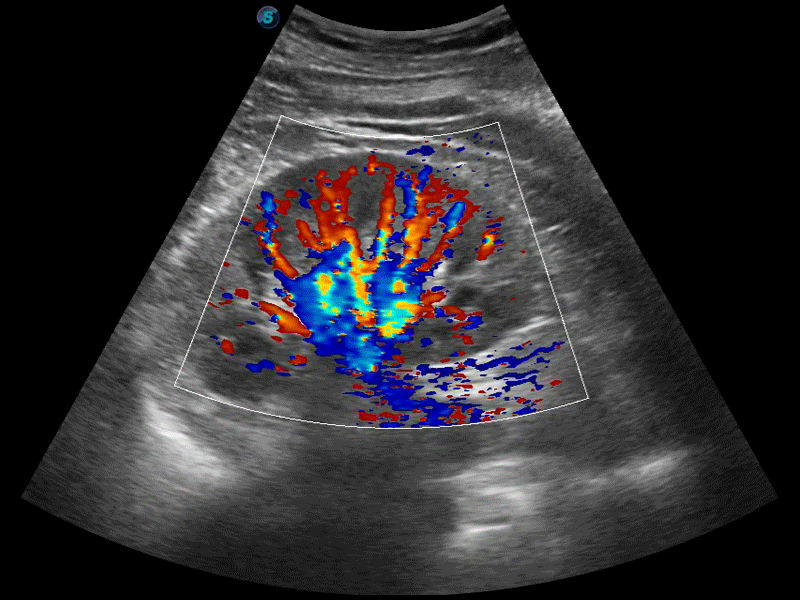

临床图像

• SR Flow高分辨率血流成像技术

高分辨率血流成像技术提高了对低速血流信号的检测能力。在提高空间分辨率的同时,也克服了血流外溢现象,为用户提供更加真实的血流动力学信息。